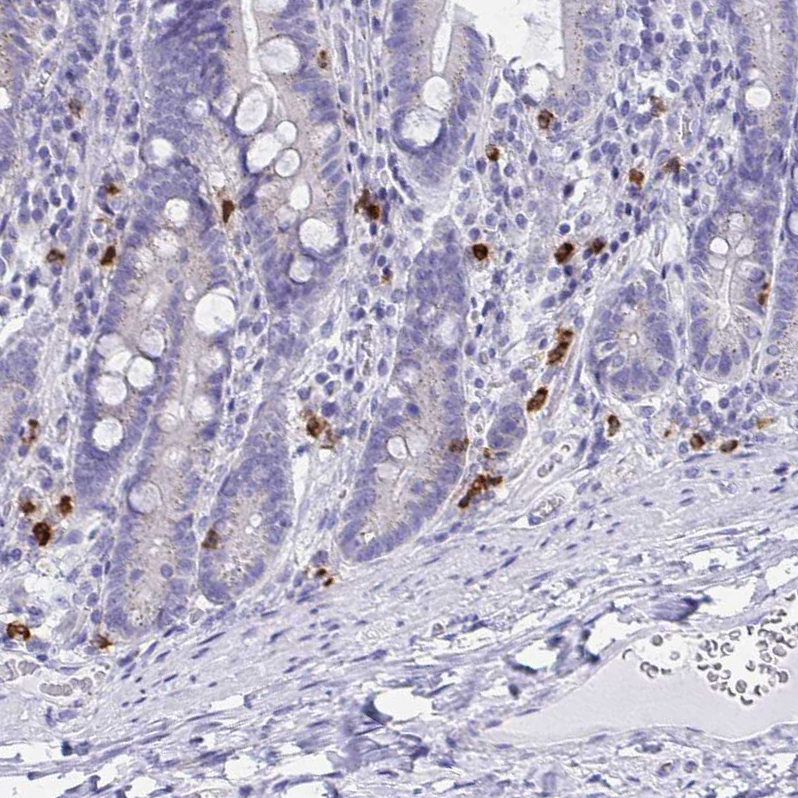

Immunohistochemistry analysis in human bone marrow and skeletal muscle tissues using HPA056183 antibody. Corresponding RNASE3 RNA-seq data are presented for the same tissues.